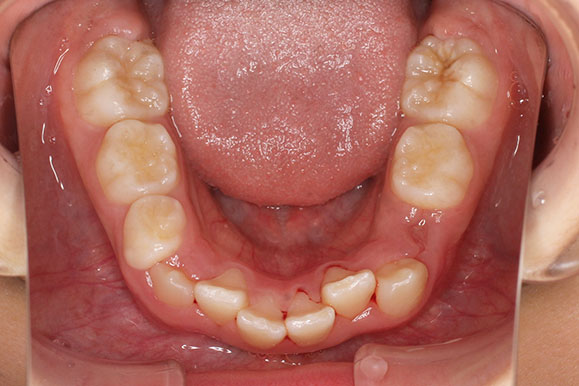

側方歯(犬歯、小臼歯)の生え変わりの時期。 前歯のがたつきを気にされ、小児矯正からの治療を希望されました。 お母様は、矯正治療経験済みですので、治療には前向きで早期治療の必要性を納得されていました。 小児矯正では、永久歯の生え変わるためのスペースを増加させ、がたつきを軽減させることを目的で行います。 残ったがたつきは、全ての永久歯が生え変わってから、本格矯正(マルチブラケット装置での治療)で改善しています。 比較的、叢生量は少ないため、本格矯正は非抜歯にて配列しました。

マルチブラケット 動的治療期間 2年6か月 調整回数16回 特に問題もなく、保定後も安定しています。